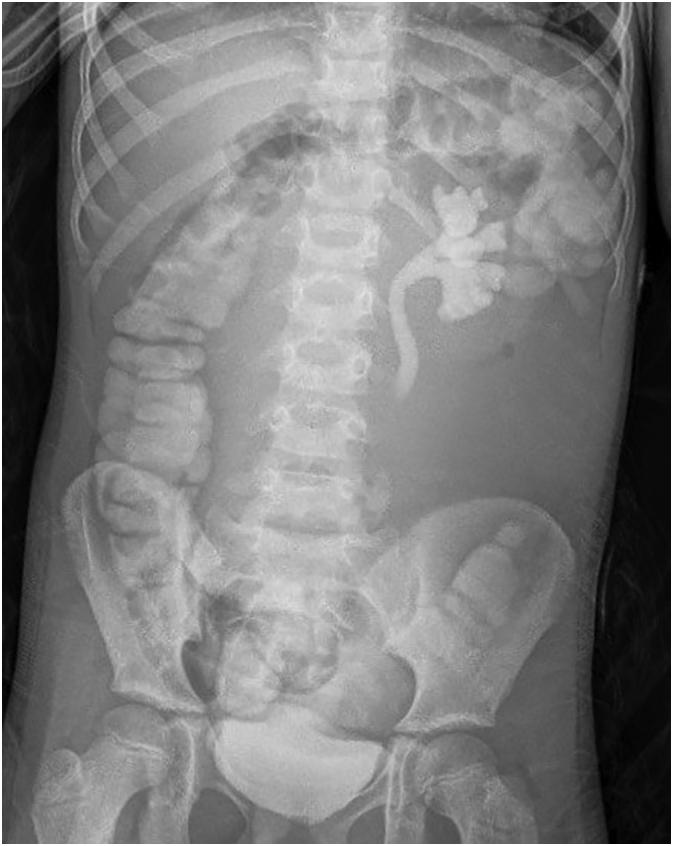

An 8-year-old female presented with five days of worsening abdominal pain, associated with nausea, vomiting, and fever, as well as vague tenderness in the right quadrants on examination. Computed tomography imaging showed a 10.5 × 8.7 × 7 cm abdominal mass, most suspicious for a cystic mass of ovarian origin. Upon diagnostic laparoscopy, a mesenteric cyst extending to the root of the mesentery was visualized and entirely resected after conversion to an exploratory laparotomy. Histopathological examination of both the cystic fluid and specimen suggest a benign mesenteric cyst.

一名8岁女性,腹痛加重5天,伴有恶心、呕吐和发热,检查时右下腹有压痛。计算机断层扫描成像显示一个10.5×8.7×7厘米的腹部肿块,最可疑为卵巢来源的囊性肿块。诊断性腹腔镜检查时,发现一个延伸至肠系膜根部的肠系膜囊肿,转为剖腹探查术后将其完全切除。对囊液和标本的组织病理学检查提示为良性肠系膜囊肿。